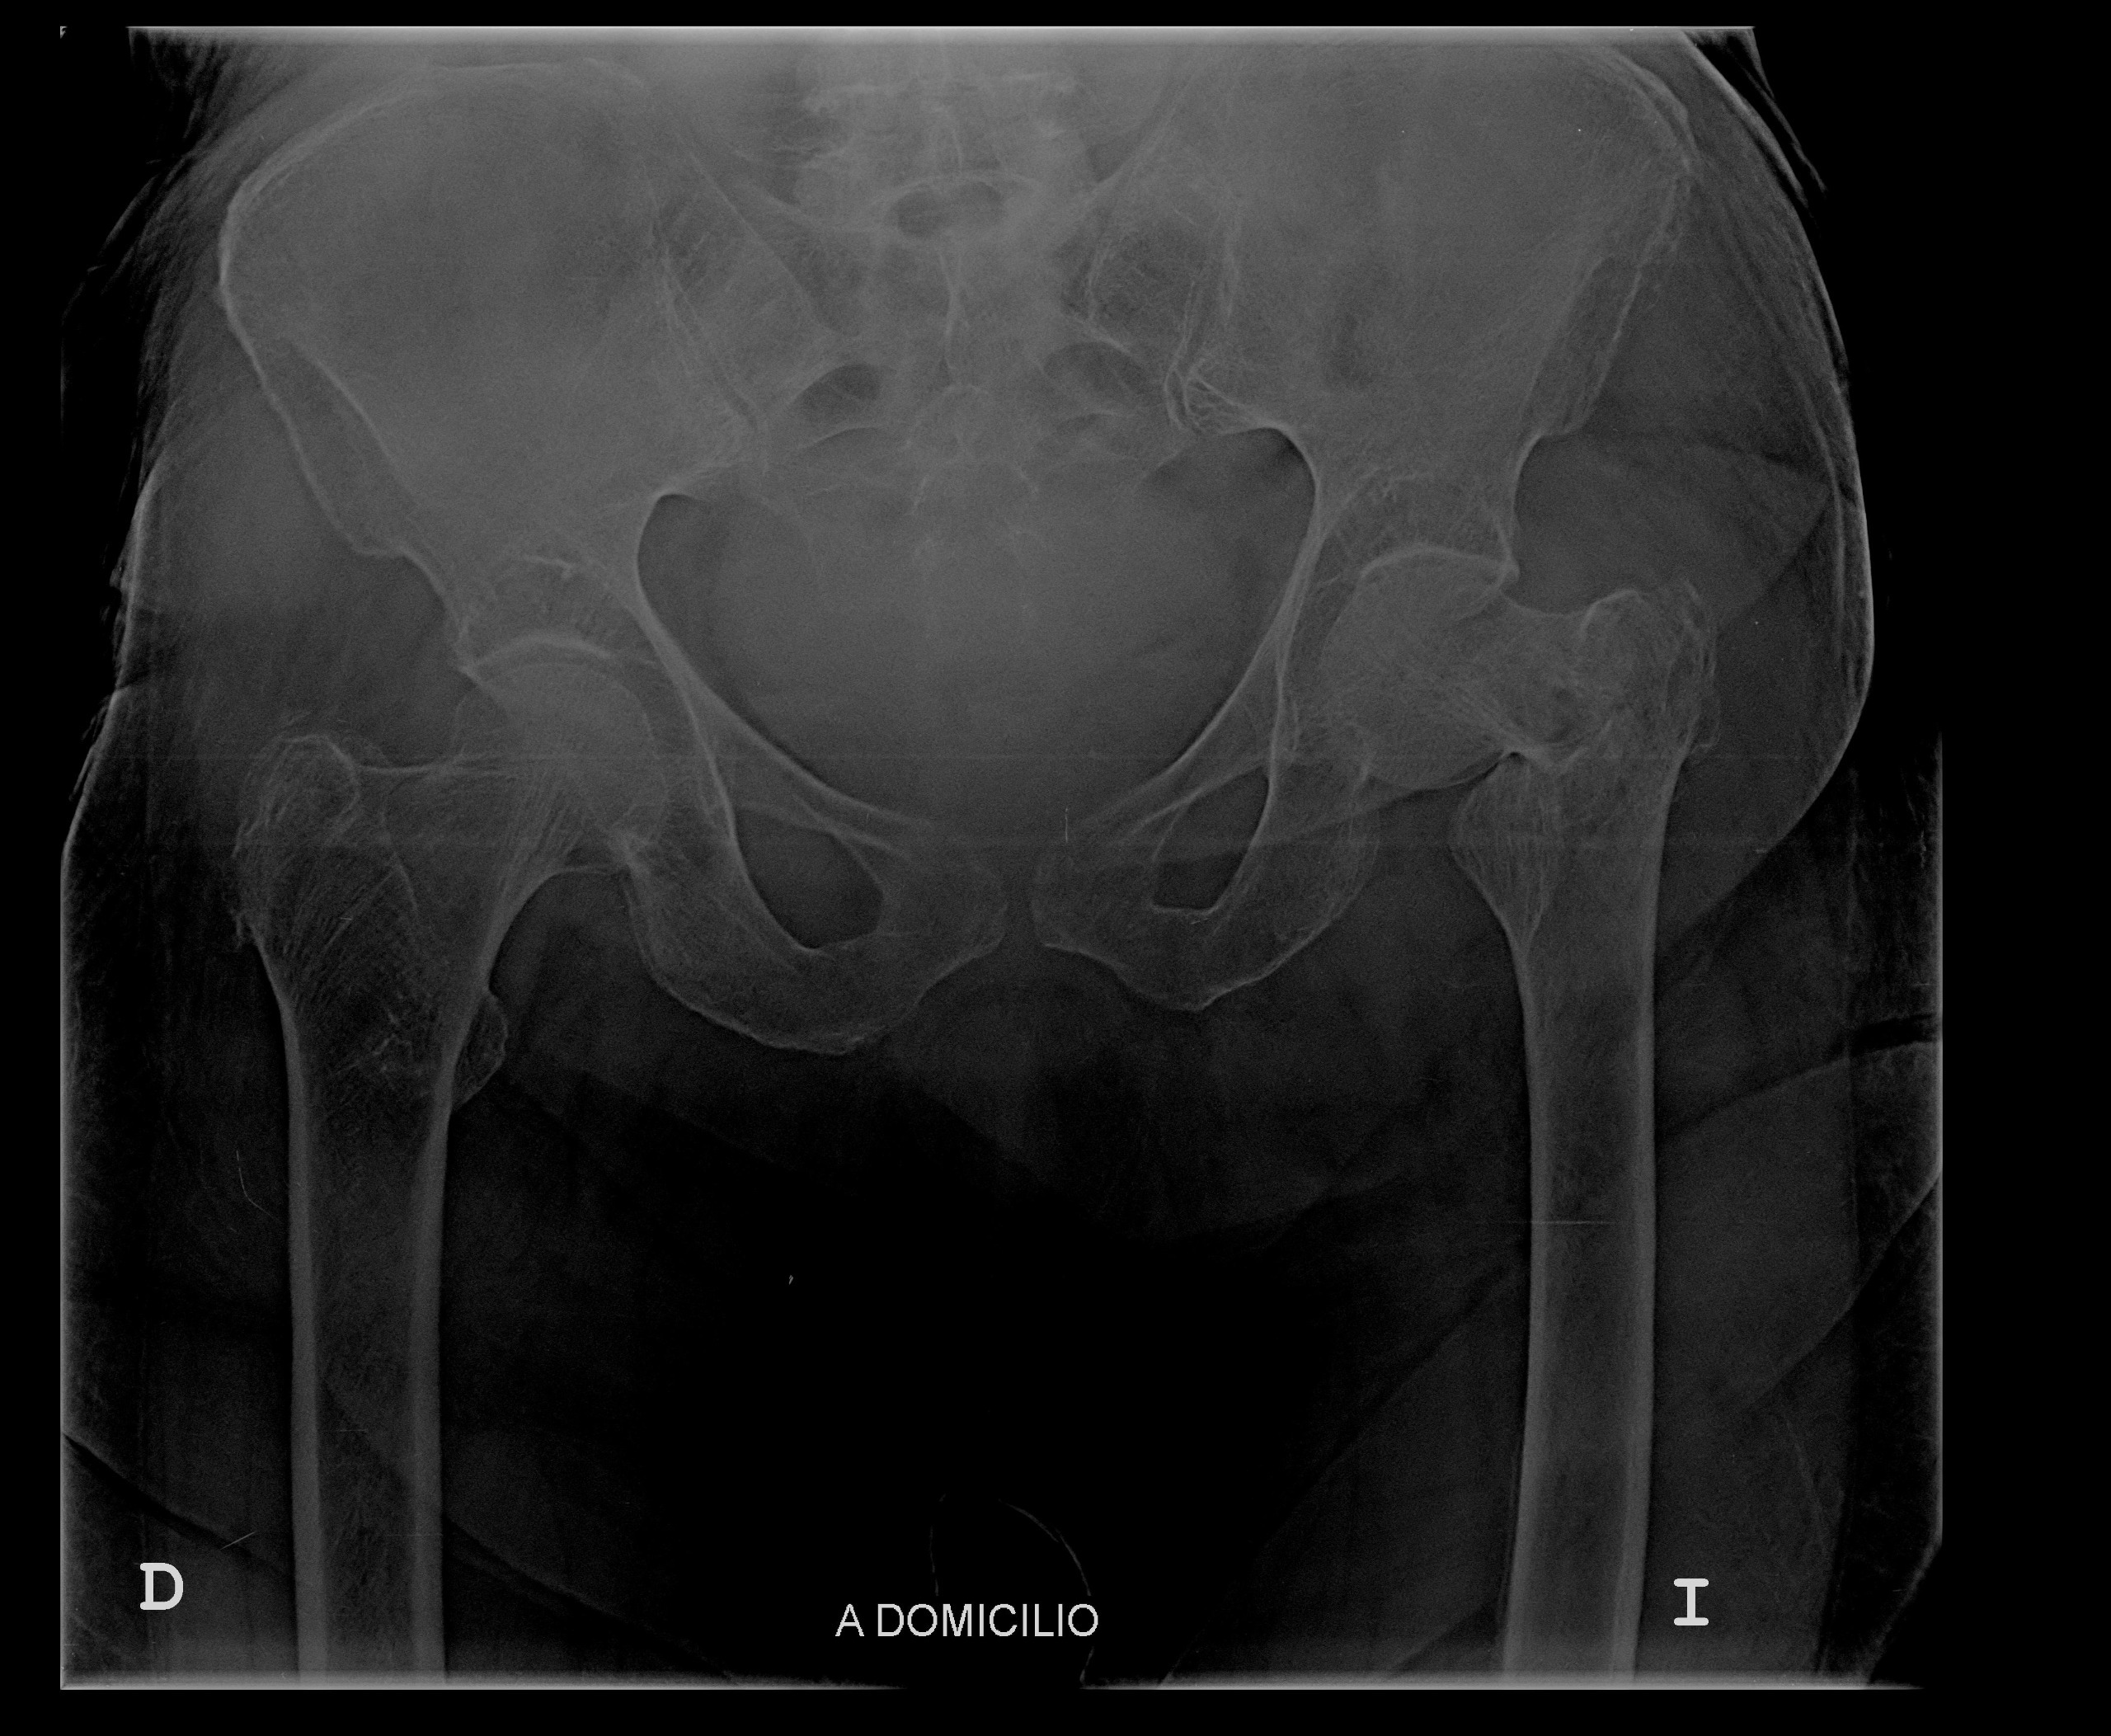

Recently, my grandmother suffered a terrible fall and fractured her left femur. She now requires extensive surgery to replace the femur, and the medical expenses are overwhelming. Our family is doing everything we can to support her, but the costs of the surgery, hospital care, and recovery are far more than we can manage alone.

Recientemente, mi abuela sufrió una fuerte caída y se fracturó el fémur izquierdo. Ahora necesita una cirugía extensa para reemplazar el hueso, y los gastos médicos son abrumadores. Aunque nuestra familia está haciendo todo lo posible para apoyarla, los costos de la cirugía, la atención hospitalaria y la recuperación superan lo que podemos manejar solos.